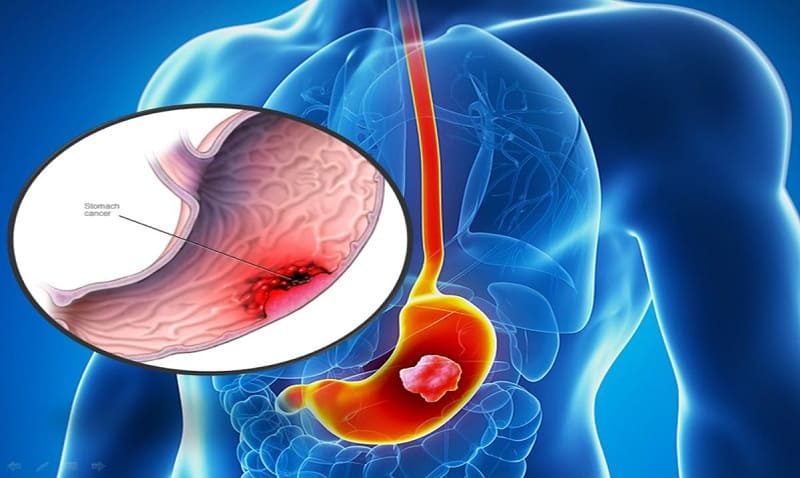

Ung thư dạ dày là một trong những bệnh ung thư phổ biến nhất hiện nay. Xét nghiệm CA 72 – 4 có thể phát hiện ung thư dạ dày ở giai đoạn sớm và có ý nghĩa trong theo dõi điều trị bệnh. Bài viết dưới đây sẽ giúp bạn đọc hiểu rõ hơn về ý nghĩa xét nghiệm này đối với vấn đề sức khỏe.

CA 72 – 4 hay cancer antigen 72 – 4 là một carbohydrate dạng nhầy có trọng lượng phân tử 16.000 dalton. Đây là một kháng nguyên được thấy trên bề mặt tế bào của vú, buồng trứng, đại tràng, tụy và đặc biệt thấy nhiều nhất ở tế bào ung thư dạ dày.

Ảnh: CA 72 – 4 là kháng nguyên được tìm thấy nhiều nhất ở tế bào ung thư dạ dày

Xét nghiệm dấu ấn ung thư dạ dày được thực hiện để chẩn đoán giai đoạn bệnh ung thư của bệnh nhân cũng như giúp theo dõi đáp ứng điều trị và tiên lượng tái phát bệnh ung thư dạ dày.